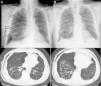

We report the case of a 67-year-old man with a history of hydropneumothorax due to pulmonary contusion and spontaneous pneumothorax, diagnosed with IPF (combined fibrosis/emphysema syndrome subtype) according to ATS/ERS 2011 clinical, radiological and functional criteria,1 treated with pirfenidone. He consulted due to chest pain, sudden onset dyspnea, with the use of accessory muscles of respiration. Examination showed loss of vesicular breath sounds in the right hemithorax, and the findings of a radiographic study were compatible with tension pneumothorax (Fig. 1A). After placement of a chest tube, the patient was transferred to the hospital ward, where a pleural space with persistent air leak was observed, despite 3 endothoracic drainage procedures (2 with fine caliber tube, 8 and 10F, and another with thick caliber tube, 24F) with no resolution of the pneumothorax.

Surgery was ruled out due to the high surgical risk posed by his parenchymal disease, so flexible fiberoptic bronchoscopy (FFB) was performed on day 21 of hospitalization, under deep sedation (patient in semi-sitting position), using a 24G chest tube in the right hemithorax with water seal to identify the absence/presence of air leak. No endoscopic changes were found in the right bronchial tree. The lateral subsegmentary bronchus (SB) of the middle lobe bronchus was accessed, which on detailed examination of the results of a computed axial tomography (CAT) scan appeared to be the origin of the air leak. A Fogarty catheter® was then used to completely collapse the SB, revealing absence of air leak. Two ml of cyanoacrylate were then instilled into the bronchus, guided by telescopic catheter, with no immediate complications. On completion of the FFB, the air leak was intermittent and progressively resolving, and no pneumothorax was observed on the chest radiograph obtained before discharge, 16 days after the procedure (Fig. 1B).